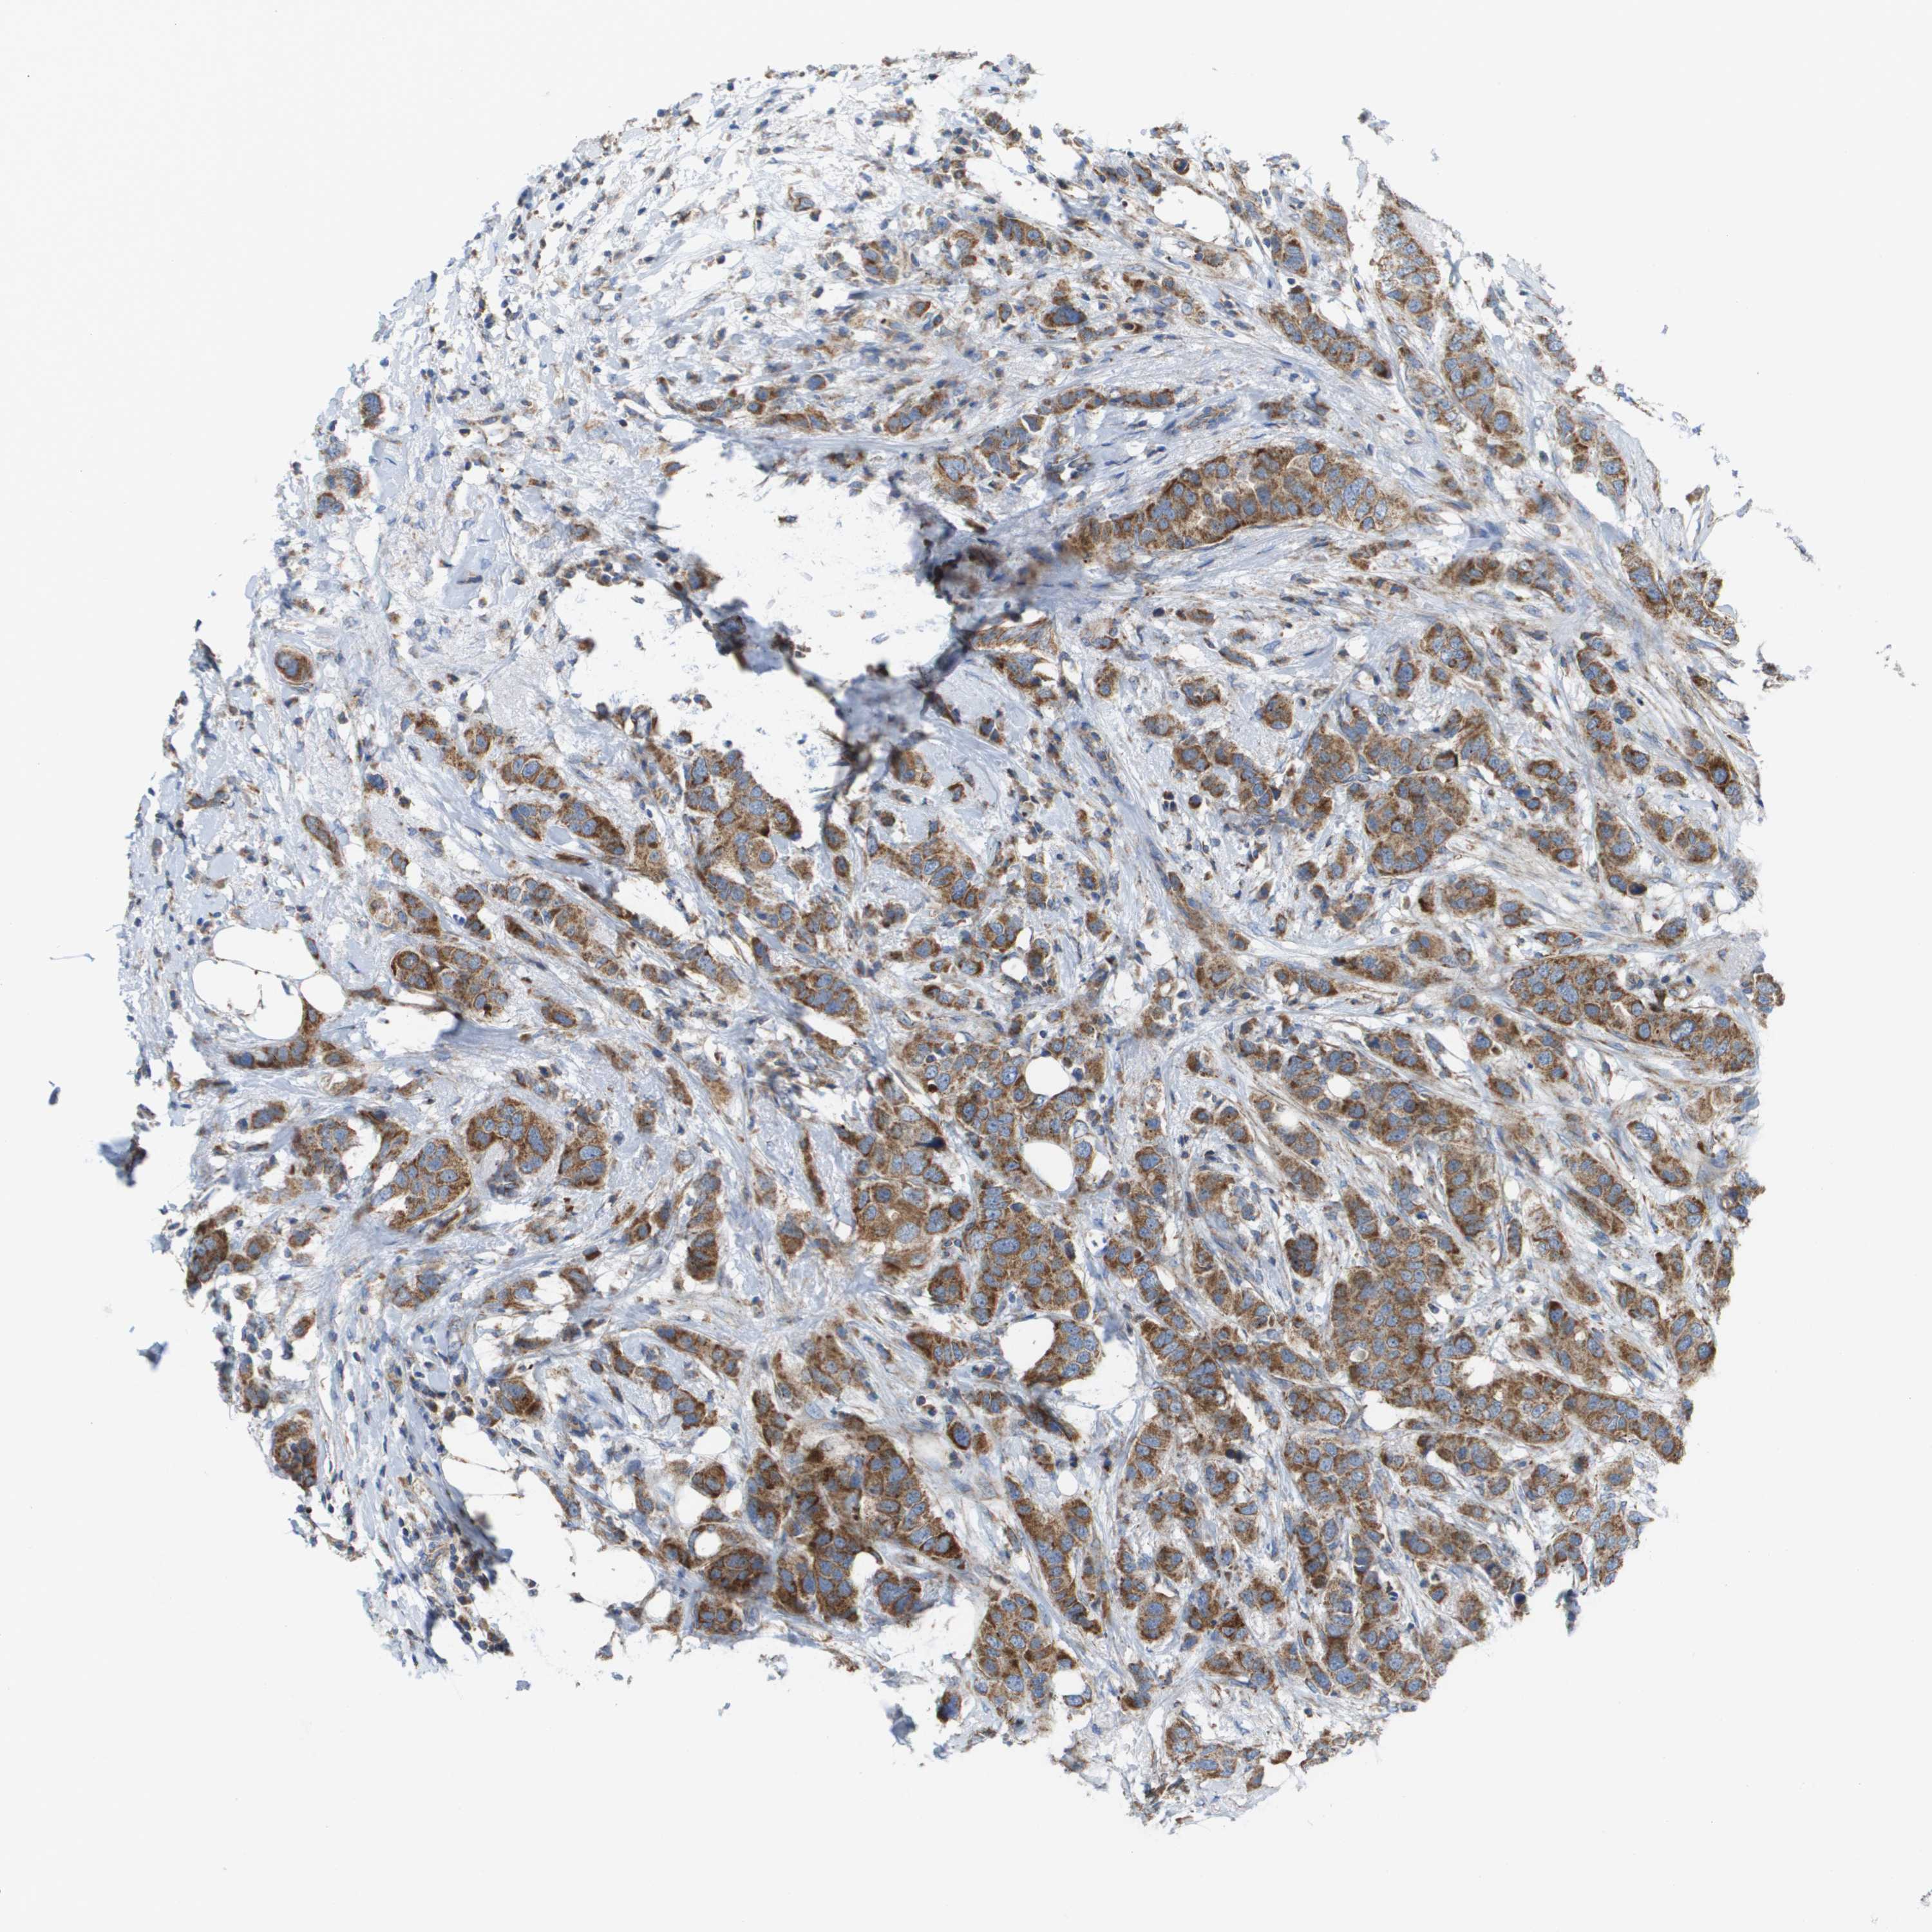

BRCA TCGA BRCA VALIDATION PROTEIN EXPRESSION

ANTIBODIES

AND

VALIDATION